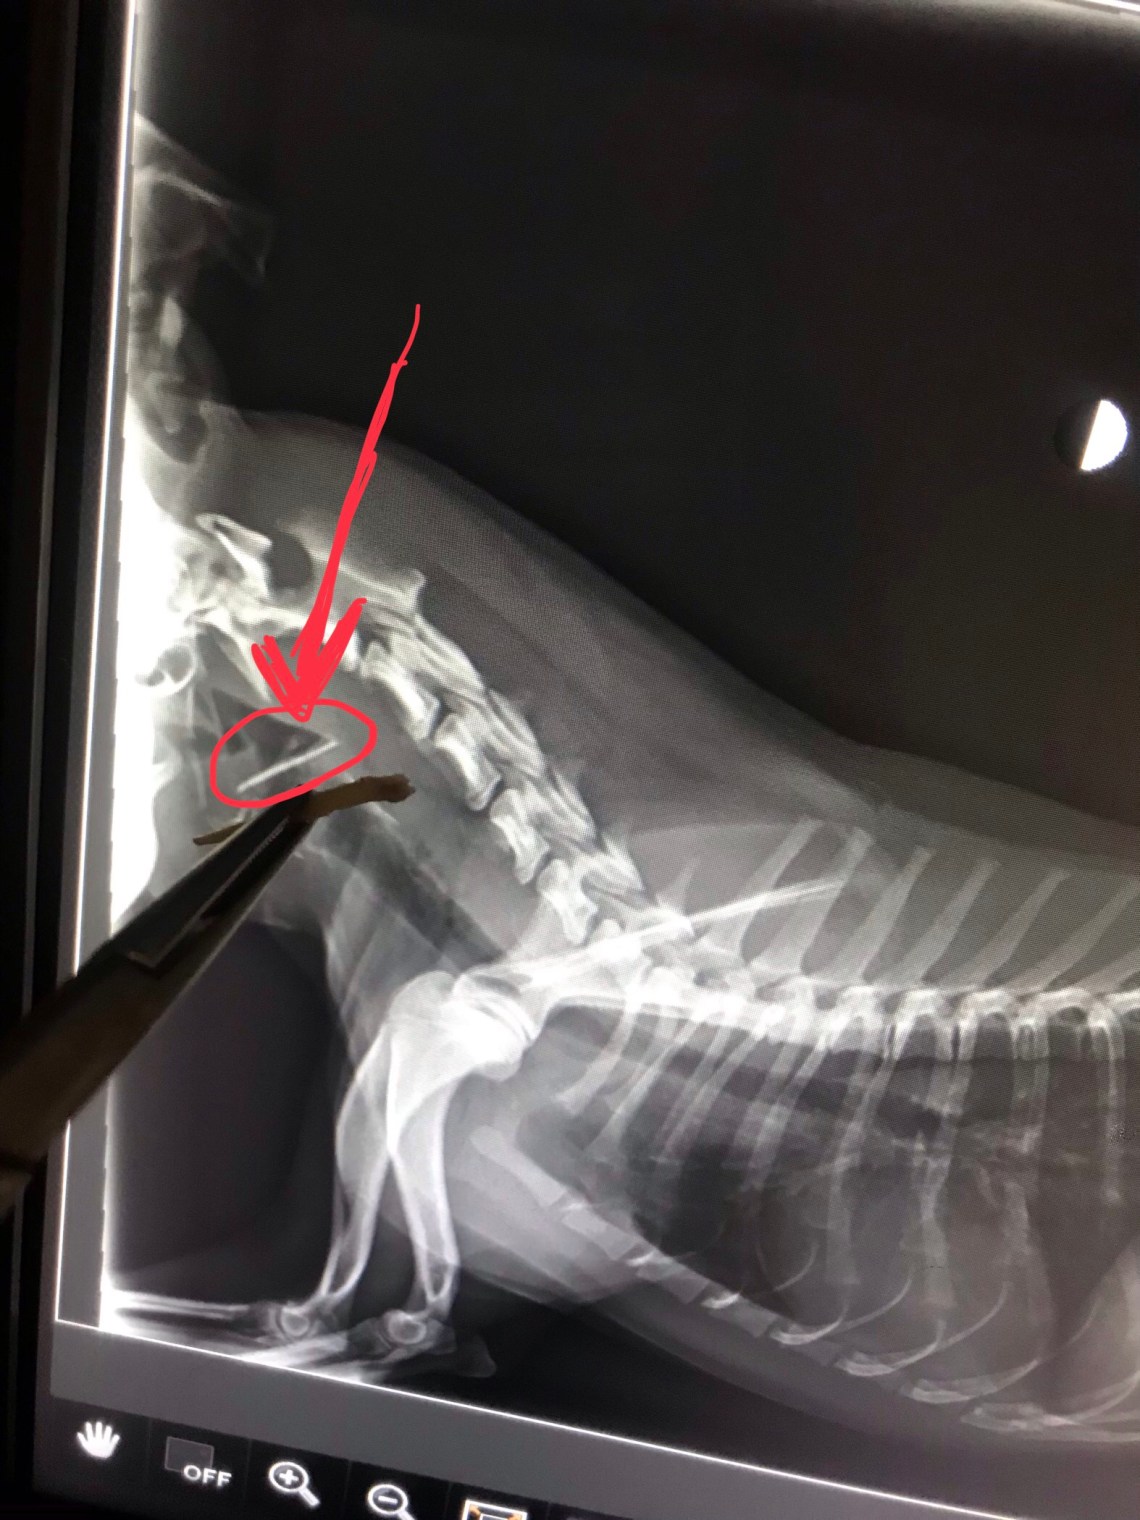

Here is a photo of a radiograph that includes the shard of chicken bone that was lodged in this dog’s throat.

He got into the garbage can and ate chicken wings.

This dog had to be fully sedated and the bone was able to be removed with a pair of forceps.

If it had been any further, there was a risk of an esophagus tear, which is a major medical issue.